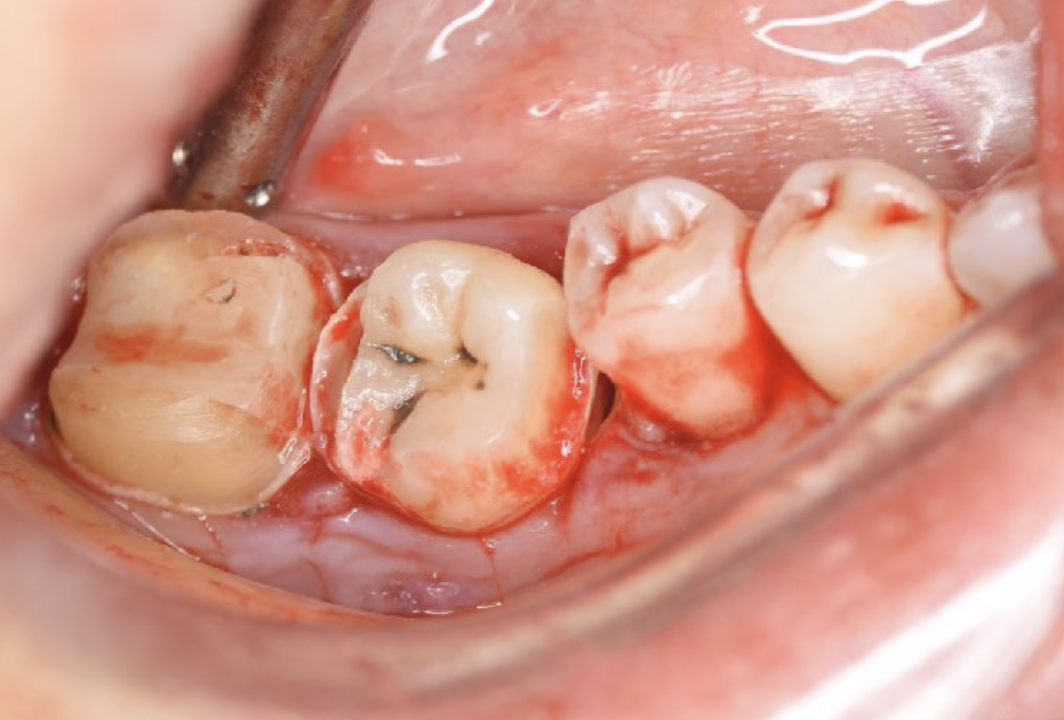

A 27-year-old female patient came to us with discomfort in the right lower jaw (Figure 1). Her primary symptoms were pain in the lower right tooth when biting and discomfort associated with not being able to chew well with the lower left single denture. The patient was married and had one young child, and previously received dental treatment in China, then had returned to Japan for childbirth and early childcare. The patient was a nonsmoker with moderate plaque control and medical history taking revealed no problems. In clinical and radiographic examinations, a root fracture was observed on tooth #46, which had been endodontic ally treated and restored with a full-cast metal crown. Periodontal probing revealed a pocket depth of 8 mm on the buccal center side of the tooth. No pain was detected with percussion and mobility of the tooth was normal. (Figure 1, Figure 2, Figure 3).

Figure 3.Preoperative intraoral findings. A metal crown was inserted at #46 and bleeding on probing during the periodontal pocket examination was noted.

The patient was given amoxicillin/clavulanic acid at 250 mg (Sawacillin Capsules, Japanese Pharmacopoeia, Japan) one hour prior to surgery. Under local anesthesia (GINGICAINE GEL, Hakusui Trading CO., LTD, Tokyo, Japan ), with an inferior alveolar nerve block used for tooth #46 alonb with 2% lidocaine and 1:80000 epinephrine (Dentsply, Tokyo, Japan), that tooth was separated and its fragments were gently extracted with a dental elevator. Granulation tissue was then removed and the socket was prepared with an internal cooling carbide bur. The graft bed was formed using the CT measurements as an index. Abundant rinsing with 0.05% chlorhexidine gluconate and sterile saline (OTSUKA NORMAL SALINE, Otsuka Pharmaceutical Factory, Inc., Tokushima, Japan) was performed to eliminate debris. Tooth #48 was gently extracted with forceps and dental elevators, and meticulously examined, and the absence of fractures was confirmed. Also, the periodontal ligament in the extracted graft tooth was observed and considered to be sufficient, then, after measuring length with a probe, it was stored in saline (Figure 4).

The tooth was immediately placed into the recipient site (Figure 5) and splinted with a methyl methacrylate (MMA)-based adhesive resin cement (Super-Bond C&B, Sun Medical; www.sun-medical.co.jp, Shiga, Japan), as there were some concerns regarding tooth stability. A 4-0 nylon suture (MANI; www.mani.co.jp, Tochigi, Japan) was used for better soft tissue adaptation and occlusal adjustment of the donor tooth was performed to remove any interference. The procedure time was 60 minutes, with time from extraction of the donor tooth until its placement in the recipient site 16 minutes (Figure 6).